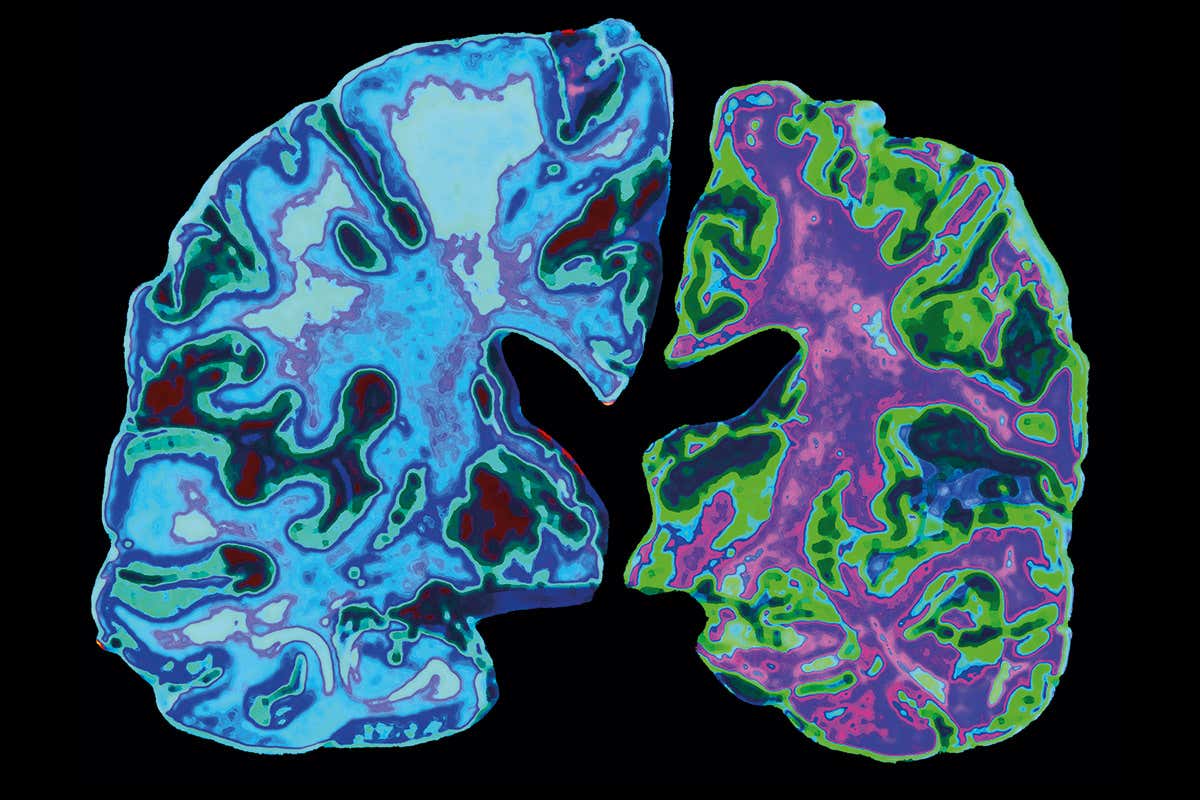

Ευτυχώς ορισμένες κλινικές δοκιμές φαρμάκων που δεν αφορούσαν την COVID-19 συνεχίστηκαν μεσούσης της πανδημίας. Ετσι, την εβδομάδα που πέρασε υπήρξε ένα καλό νέο για τους ασθενείς με νόσο Αλτσάιμερ: ο Οργανισμός Τροφίμων και Φαρμάκων των ΗΠΑ έδωσε την έγκρισή του για την κυκλοφορία ενός φαρμάκου το οποίο διαλύει τις χαρακτηριστικές για τη νόσο πλάκες του αμυλοειδούς (των συσσωματωμάτων στον εγκέφαλο των ασθενών της ομώνυμης πρωτεΐνης, τα οποία θεωρούνται αιτία καταστροφής των νευρικών κυττάρων).

Το νέο φάρμακο, το οποίο χορηγείται ενδοφλέβια μία φορά κάθε τέσσερις εβδομάδες, δεν είναι φθηνό: το ετήσιο κόστος του υπολογίζεται γύρω στις 56.000 δολάρια! Και όπως φαίνεται από τις κλινικές δοκιμές μάλλον καθυστερεί την εξέλιξη, αλλά δεν θεραπεύει τη νόσο. Ωστόσο η κυκλοφορία του εκτιμάται ως μεγάλη πρόοδος καθώς πρόκειται για την πρώτη έγκριση φαρμάκου για την Αλτσχάιμερ τα τελευταία 20 χρόνια! Και όλα αυτά, παρά το γεγονός ότι η δεκαετία του 1990 είχε ονομαστεί δεκαετία του εγκεφάλου και ο τότε αμερικανός πρόεδρος (Μπους ο πρεσβύτερος) είχε υποσχεθεί νίκη κατά κράτος έναντι της νόσου και σημαντική κρατική και ιδιωτική χρηματοδότηση είχε διατεθεί προς αυτή την κατεύθυνση.